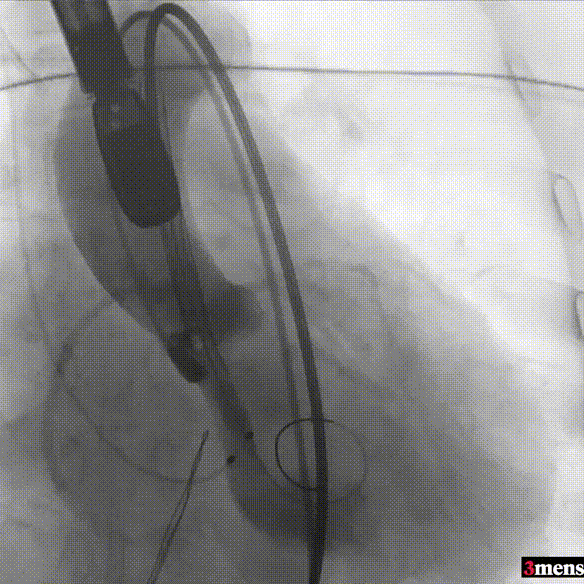

手术过程回顾:

患者全麻后,右侧股动脉建立主入路,主动脉根部造影显示主动脉瓣无明显钙化。心室内轻中量反流,主动脉及心脏情况整体较为稳定,根据术前策略预装23mm瓣膜。超硬置入左心室后,因超硬压迫无冠瓣叶导致急性反流,病人血压降至40mmHg,遂迅速将输送器送入主动脉根部,快速释放瓣膜后,病人血压恢复至正常。瓣膜脱钩后造影显示左冠开口存在一定狭窄,IVUS评估左冠开口狭窄约60%,符合PCI指征,植入开窗支架改善狭窄,最终再次造影加IVUS评估左冠开口,确定狭窄解除。

右侧股动脉穿刺

主动脉根部造影

直头导丝跨瓣

跨瓣压差测量

输送器定位

完全释放后造影疑似左冠狭窄

IVUS探查左冠开口狭窄60%

放置开窗支架

球囊后扩支架

假体瓣膜形态良好,无明显瓣周漏

术后测量跨瓣压差仅为1mmHg